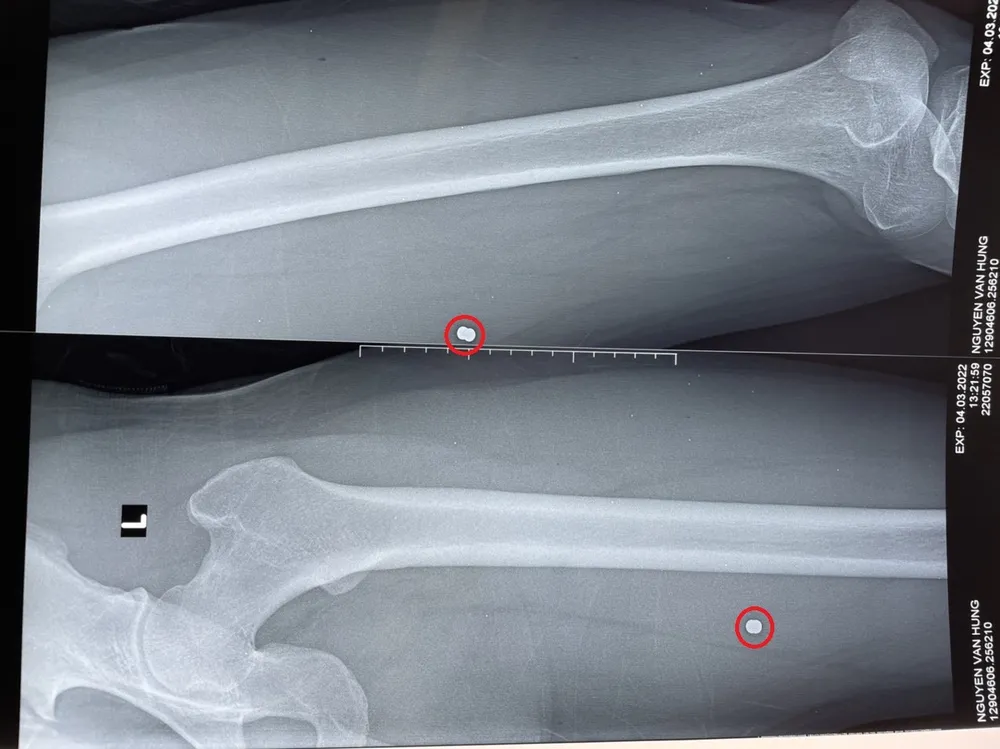

Hình ảnh X-quang đầu đạn trong đùi bệnh nhân. Ảnh: BVCC

Tại bệnh viện, các bác sĩ tiến hành sơ cứu kiểm tra vết thương, xử trí cấp cứu xác, định đường di chuyển và tìm dị vật nghi ngờ là viên đạn. Kết quả chụp X-quang ghi nhận xương đùi trái bệnh nhân có dị vật, nghi là đầu đạn bằng kim loại trong mô mềm vị trí 1/3 trên đùi trái.